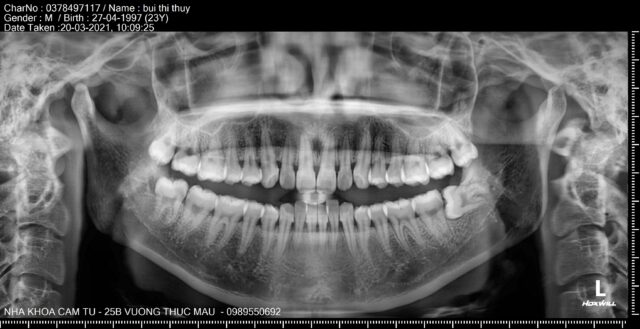

- Hệ thống máy chụp phim 3D Cone Beam hiện đại, phát hiện chính xác vị trí răng khôn mọc lệch, mọc ngầm.

- Bước 1: Khám tổng quát và chụp phim X-quang.